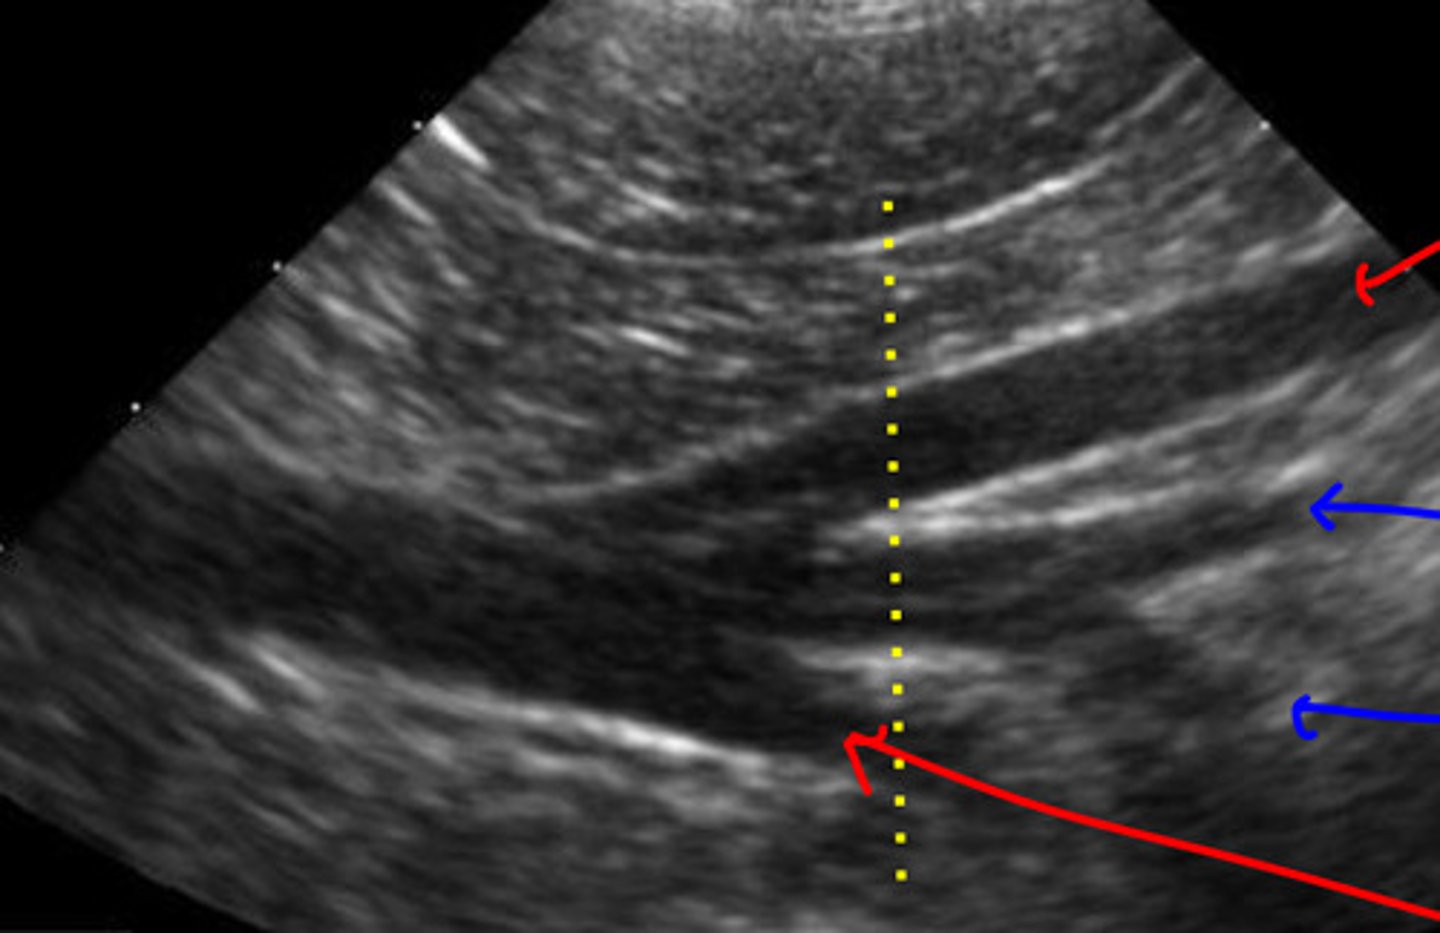

red- vena cava

blue- aorta

red- right side of body

blue- left side of body

orientation- transverse b/c round

ID red and blue, which one is on the right side of the body and which is on the left? what orientation is this?

red- caudal vena cava

blue- aorta

what is the red and blue vasculature?